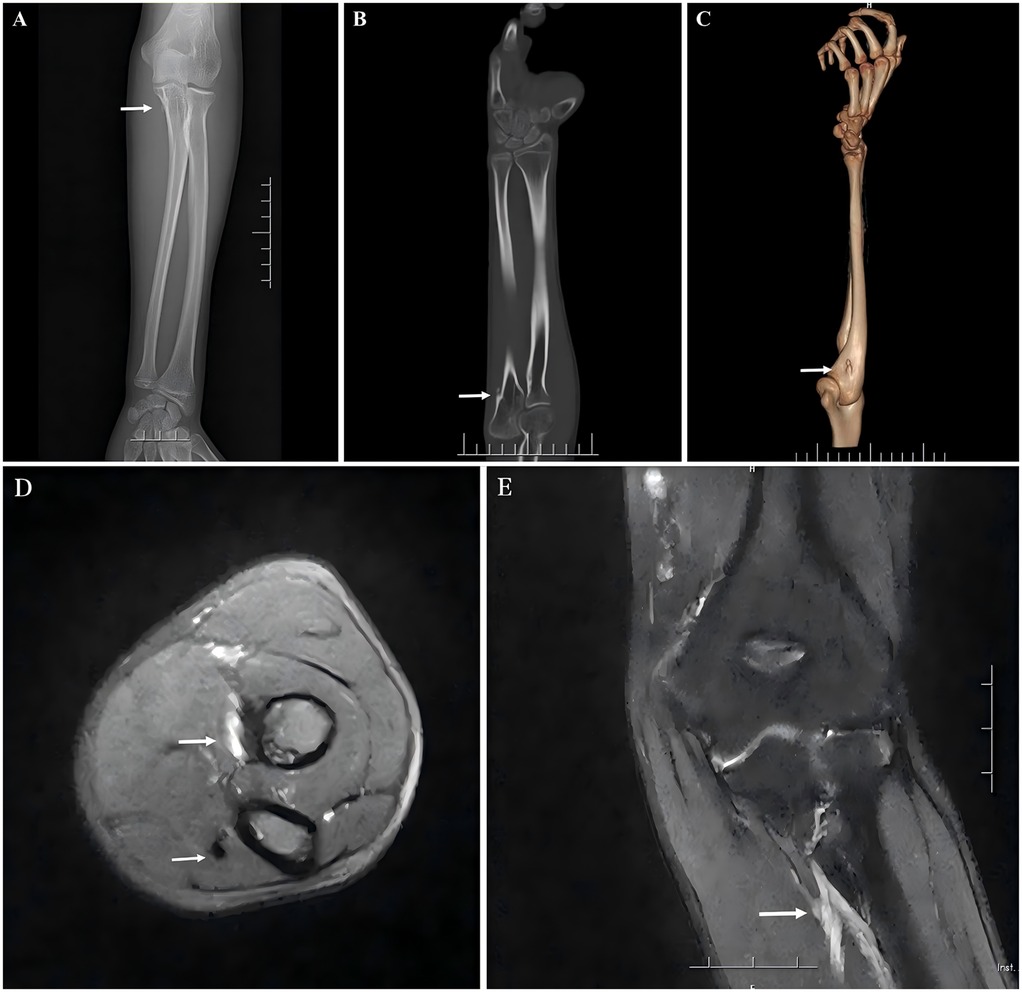

The anteroposterior x-ray, 3D CT, and MRI of the forearm (Figure 2) show that a small, approximately 0.4 cm long nodular bony process was revealed on the proximomedial aspect of the left ulna, with a broad base extending dorsally toward the articular surface. A hyperintense lesion was revealed in the deep layer of the proximal forearm muscles through T2-weighted magnetic resonance imaging of the forearm, along with thickened fiber bundles at the ulnar attachment of the flexor digitorum profundus. Based on his symptoms and auxiliary examinations, we reached a diagnosis: congenital progressive contracture of the flexor digitorum profundus in the forearm.

Images A, B, and C show X-ray and 3D CT scans of the patient's left forearm. Imaging reveals a bony prominence on the medial aspect of the proximal left ulna, originating from the ulnar cortical surface and extending distally. Images D and E show MRI of the patient's left forearm, demonstrating a high-signal lesion within the deep muscle layer of the proximal forearm and an abnormal fibrous cord within the flexor digitorum profundus tendon.

Figure 2. (A,C) x-ray and 3D CT scans reveal a bony prominence on the medial aspect of the proximal ulna (indicated by arrow). (B) The coronal CT scan of the ulna shows that the bony prominence originates from the cortical surface of the ulna, extending distally (indicated by arrow). (D) MRI shows a high-intensity lesion in the deep muscle layer of the anterior proximal forearm and an abnormal fibrous cord in the flexor digitorum profundus. (E) A high-intensity lesion in the deep muscle layer of the anterior proximal forearm.